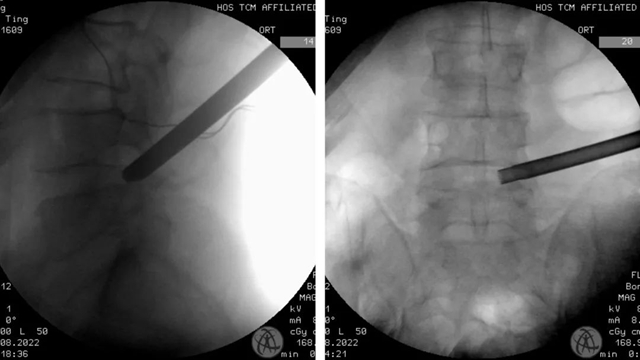

经过影像学检查,结果显示彭大叔的腰椎没有出现不稳定、滑脱等其他情况,李森教授认为非常适合微创手术,决定为患者在腰部局麻下行“内镜下腰椎间盘突出髓核摘除术”。

手术历时40分钟,腰部局部麻醉后,打了一个不到1cm的“小洞”。术中出血少,创口小,术后第二天佩戴腰部护具即可下地行走。